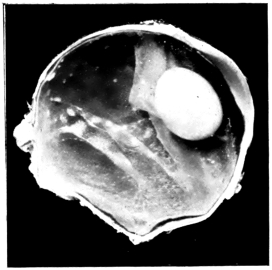

PLATE V.

28.

INJURIES TO UVEAL TRACT

curly bracket span

54

29.

FOREIGN BODY (TIP OF COPPER PROBE) IMBEDDED IN THE EYE

30.

TRAUMATIC DETACHMENT OF RETINA AND CHOROID

31.

WHOLE-SECTION OF FIG. 19

32.

PART OF THE ABOVE MAGNIFIED TO SHOW LENS IMBEDDED IN INFLAMMATORY EXUDATE

33.

PHAGOCYTOSIS